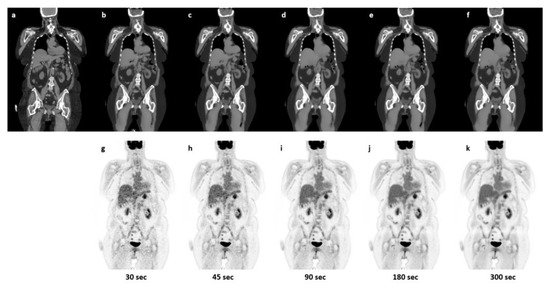

3.1. Qualitative Evaluation

3.2. Quantitative Evaluation